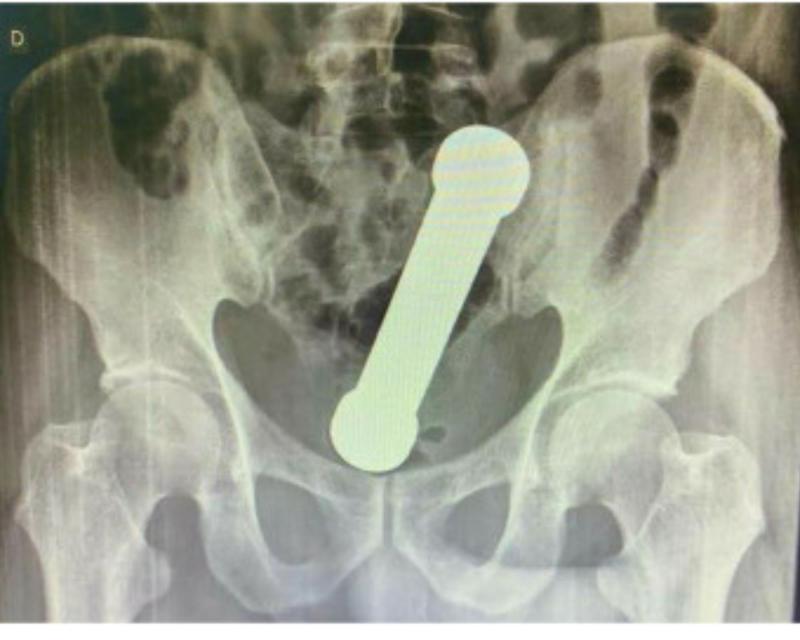

Las radiografías abdominales revelaron que el hombre tenía una mancuerna de 20 centímetros atorada a la altura del lugar en que el colon se conecta con el recto.